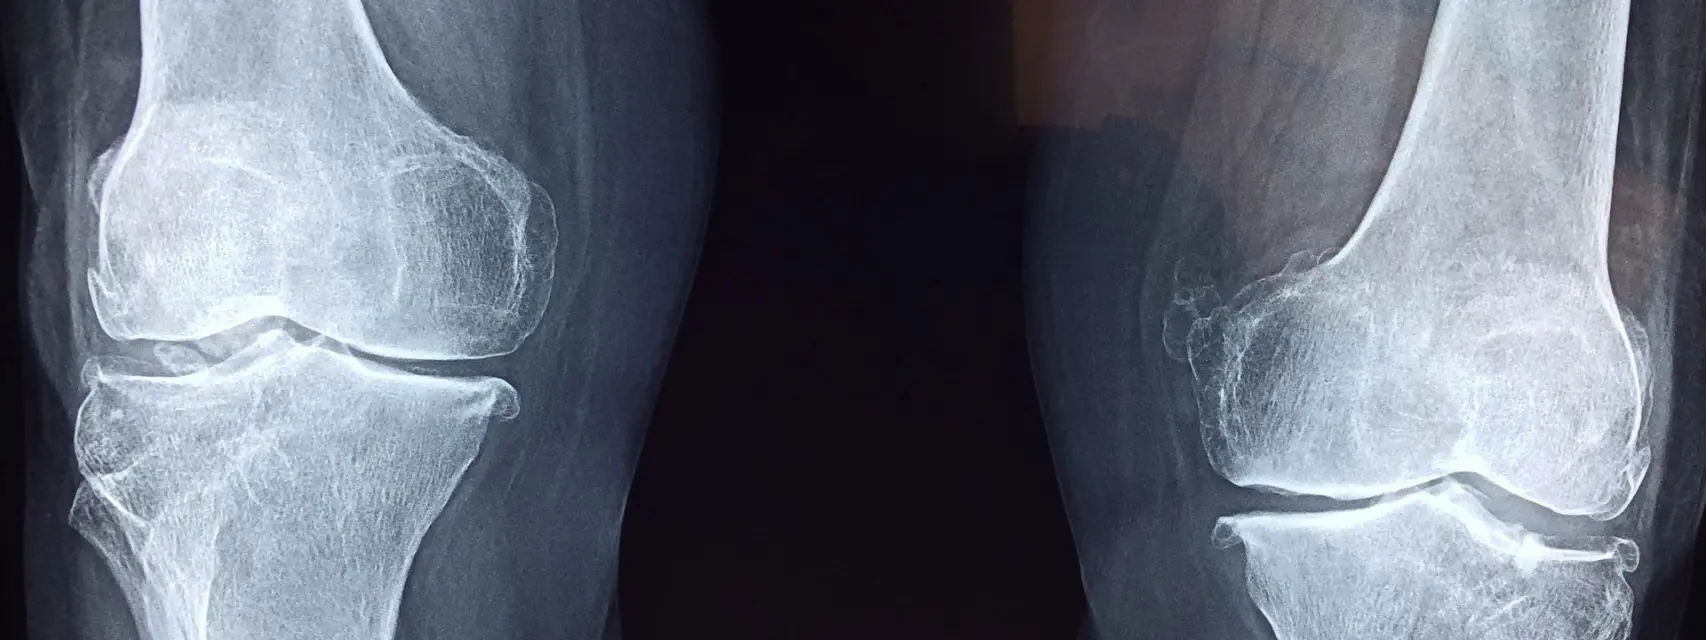

Así debilita los huesos la exposición a químicos presentes en el agua y otros productos cotidianos

Publicado el marzo 17, 2026 10:06 amLos PFAS, también conocidos como “tóxicos eternos”, son una de las familias de químicos más utilizadas hoy por la industria. Están presentes […]